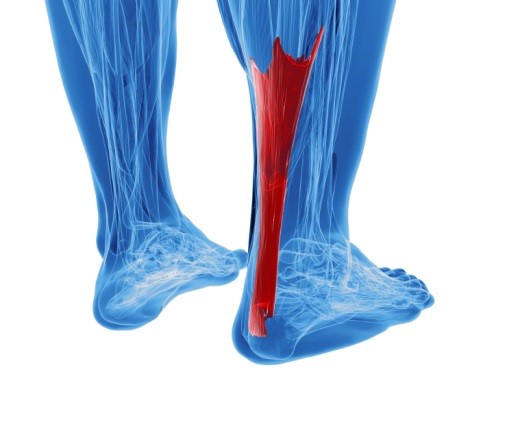

If you are always on your feet, heel pain may be a common occurrence. Changing your fitness routine or putting on a few pounds can also add pressure to the feet, resulting in heel pain. Discomfort in the feet should never be overlooked, but heel pain can often be resolved through stretching. Properly flexing and exercising the muscles in your lower extremity can strengthen and protect your heels and other areas of the foot from future pain.

If you are always on your feet, heel pain may be a common occurrence. Changing your fitness routine or putting on a few pounds can also add pressure to the feet, resulting in heel pain. Discomfort in the feet should never be overlooked, but heel pain can often be resolved through stretching. Properly flexing and exercising the muscles in your lower extremity can strengthen and protect your heels and other areas of the foot from future pain.

● Heel pain is often associated with plantar fasciitis. The plantar fascia is a band of tissues that extends along the bottom of the foot. A rip or tear in this ligament can cause inflammation of the tissue.

● Achilles tendonitis is another cause of heel pain. Inflammation of the Achilles tendon will cause pain from fractures and muscle tearing. Lack of flexibility is also another symptom.

● Heel spurs are another cause of pain. When the tissues of the plantar fascia undergo a great deal of stress, it can lead to ligament separation from the heel bone, causing heel spurs.

Heel pain should be treated as soon as possible for immediate results. Keeping your feet in a stress free environment will help. If you suffer from Achilles tendonitis or plantar fasciitis, applying ice will reduce the swelling. Stretching before an exercise like running will help the muscles. Using all these tips will help make heel pain a thing of the past.